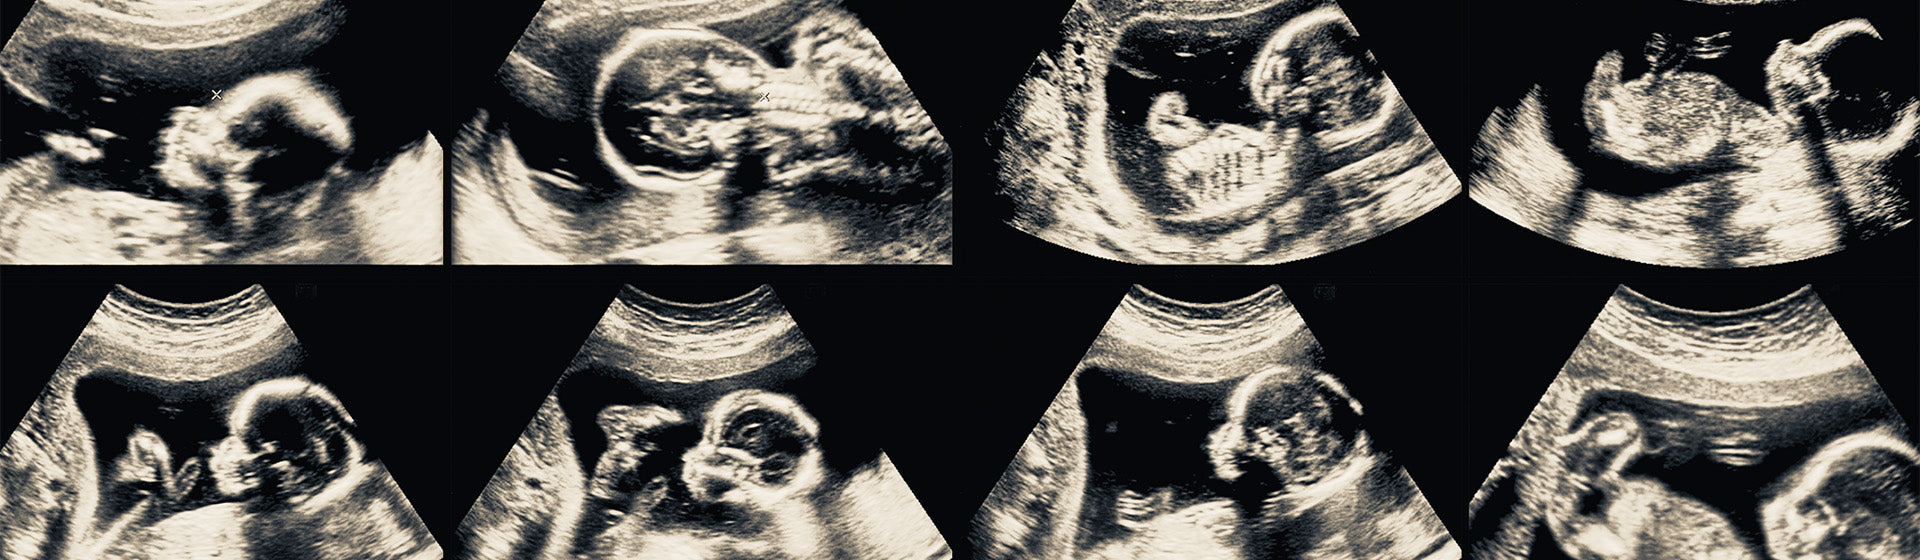

- Première échographie : généralement entre la 8e et la 12e semaine de grossesse, pour confirmer la grossesse, dater le début de la grossesse et vérifier le nombre de bébés. Si vous avez des symptômes de grossesse, vous pouvez également en parler à votre médecin.

- Deuxième échographie : vers la 20e semaine, pour examiner de près le développement du bébé et détecter d'éventuelles anomalies.

- Troisième échographie : parfois effectuée vers la 32e semaine pour évaluer la croissance du bébé et la quantité de liquide amniotique.

Dans de tels cas, pour établir le terme de la grossesse avec plus de précision, on se base sur l'échographie réalisée au cours du premier trimestre, qui permet un calcul plus précis avec une marge d'erreur d'environ 3 à 5 jours.